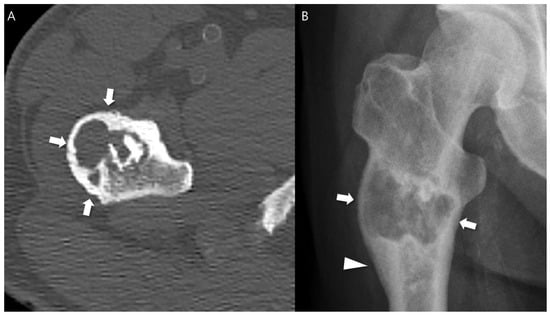

Any aggressive CT features for the grading of central cartilaginous bone tumors including (i) deep endosteal scalloping ≥ 2/3 of the normal cortical thickness (Figure 1), (ii) extensive endosteal scalloping ≥ 2/3 of the lesion length (Figure 2), (iii) expansile cortical remodeling (Figure 3), and (iv) cortical destruction with or without soft tissue extension (Figure 4) were also evaluated. The CT images were evaluated in conjunction with the plain radiographs and/or MRI. After finishing the independent review, a consensus review of the CT was performed. The two radiologists reviewed the CT images together to reach a final consensus on discrepant interpretations from the independent reading.

Figure 3. Expansile cortical remodeling in a patient with CS2 in the proximal femur. (A) An axial CT image shows a lobulated mass containing chondroid matrix mineralization and expansile cortical remodeling (arrows). (B) A plain radiograph shows a lobulated mass with expansile cortical remodeling (arrows) with cortical thickening (arrowhead).